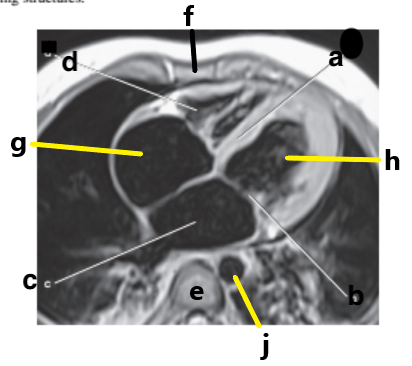

What is letter b ?

Esophagus

Left ventricle

What is letter a ?

Left atrium

Right ventricle

What is letter h ?

What is letter d ?